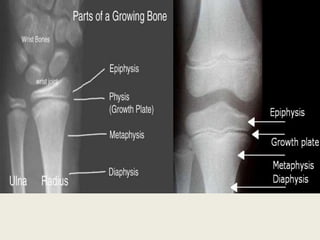

Growth Plate in Wrist & Hand | Rocky Mountain Hospital for ... Symptoms of an Injured Hand or Wrist Growth Plate . Symptoms associated with an injured growth plate in the hand include: Swelling and bruising; Severe pain; Stiffness; Inability to apply pressure to the hand and/or wrist; Bones that appear misshapen or out of place ; Treating a Fractured Growth Plate in the Wrist or Hand . Depending on the severity of the injury, a Pediatric Orthopedic Specialist may be consulted. en.wikipedia.org › wiki › History_of_watchesHistory of watches - Wikipedia The history of watches began in 16th-century Europe, where watches evolved from portable spring-driven clocks, which first appeared in the 15th century.. The watch was developed by inventors and engineers from the 16th century to the mid-20th century as a mechanical device, powered by winding a mainspring which turned gears and then moved the hands; it kept time with a rotating balance wheel. Growing bones, growing concerns: A guide to growth plates ... On an x-ray, growth plates look like dark lines at the ends of the bones. At the end of growth, when the cartilage completely hardens into bone, the dark line will no longer be visible on an x-ray. At that point growth plates are considered closed. Typically, girls' growth plates close when they're about 14-15 years old on average. Growth Plate Injuries (Physeal Fractures) by Dr. David Nelson The physis is the growth plate, the part of the bone that has the cells that allows the bone to grow longer. The metaphysis is the broad region of bone right next to the physis. The diaphysis is the narrow center part of the bone. The growth plate is made up of a special kind of cartilage called (surprise!) growth plate cartilage.

Growth Plate Fractures - OrthoInfo - AAOS Growth plates are found in the long bones of the body—the bones that are longer than they are wide. Examples of long bones include the femur (thighbone), the radius and ulna in the forearm, as well as the metacarpal bones in the hands. This diagram of a femur shows the location of the growth plates at both ends of the bone.

The Growth Plate - Connecticut Orthopaedics The physis is the growth plate, the part of the bone that has the cells that allows the bone to grow longer. The metaphysis is the broad region of bone right next to the physis. The diaphysis is the narrow center part of the bone. The growth plate is made up of a special kind of cartilage called (surprise!) growth plate cartilage.